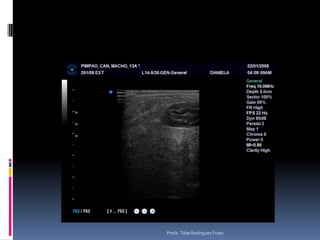

Afecções trato genital Fêmeas: Hemometra, mucometra e piometraPesquisar região de ováriosMachos: Hiperplasia prostática, nódulos e massas testicularesDificuldades – Hiperplasia prostática diferenciar de prostatite bacteriana associadaProfa. Tilde Rodrigues Froes

Animal: July, canino, Fêmea, Poodle, 10 anos, corrimento vaginal - sanguinolentoProfa. Tilde Rodrigues Froes

Afecções trato genitalFêmeas: Hemometra, mucometra e piometraPesquisar região de ováriosMachos: Hiperplasia prostática, nódulos e massas testicularesDificuldades – Hiperplasia prostática diferenciar de prostatite bacteriana associadaProfa. Tilde Rodrigues Froes

Animal: July, canino,Fêmea, Poodle, 10 anos, corrimento vaginal - sanguinolentoProfa. Tilde Rodrigues Froes